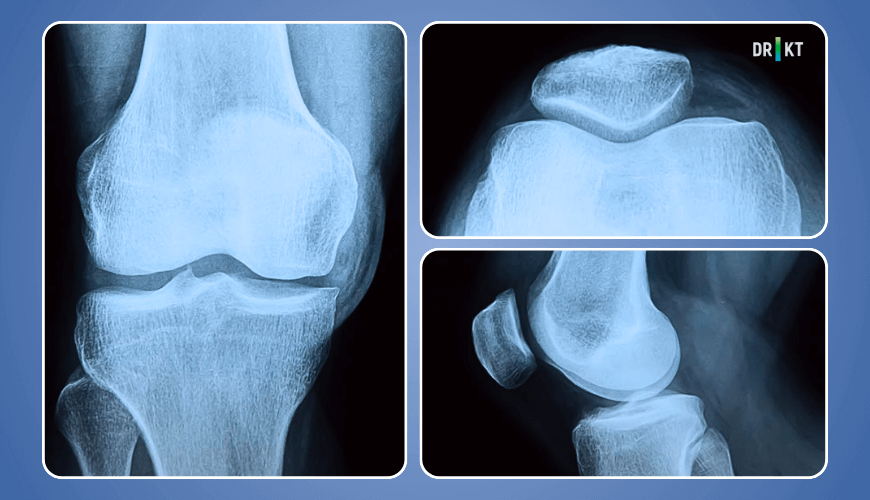

Diz kapağı ağrınızın nedenini belirlemeye yardımcı olmak için röntgen, bilgisayarlı tomografi (BT) ve MR gibi görüntüleme testleri istenebilir (Resim 3).